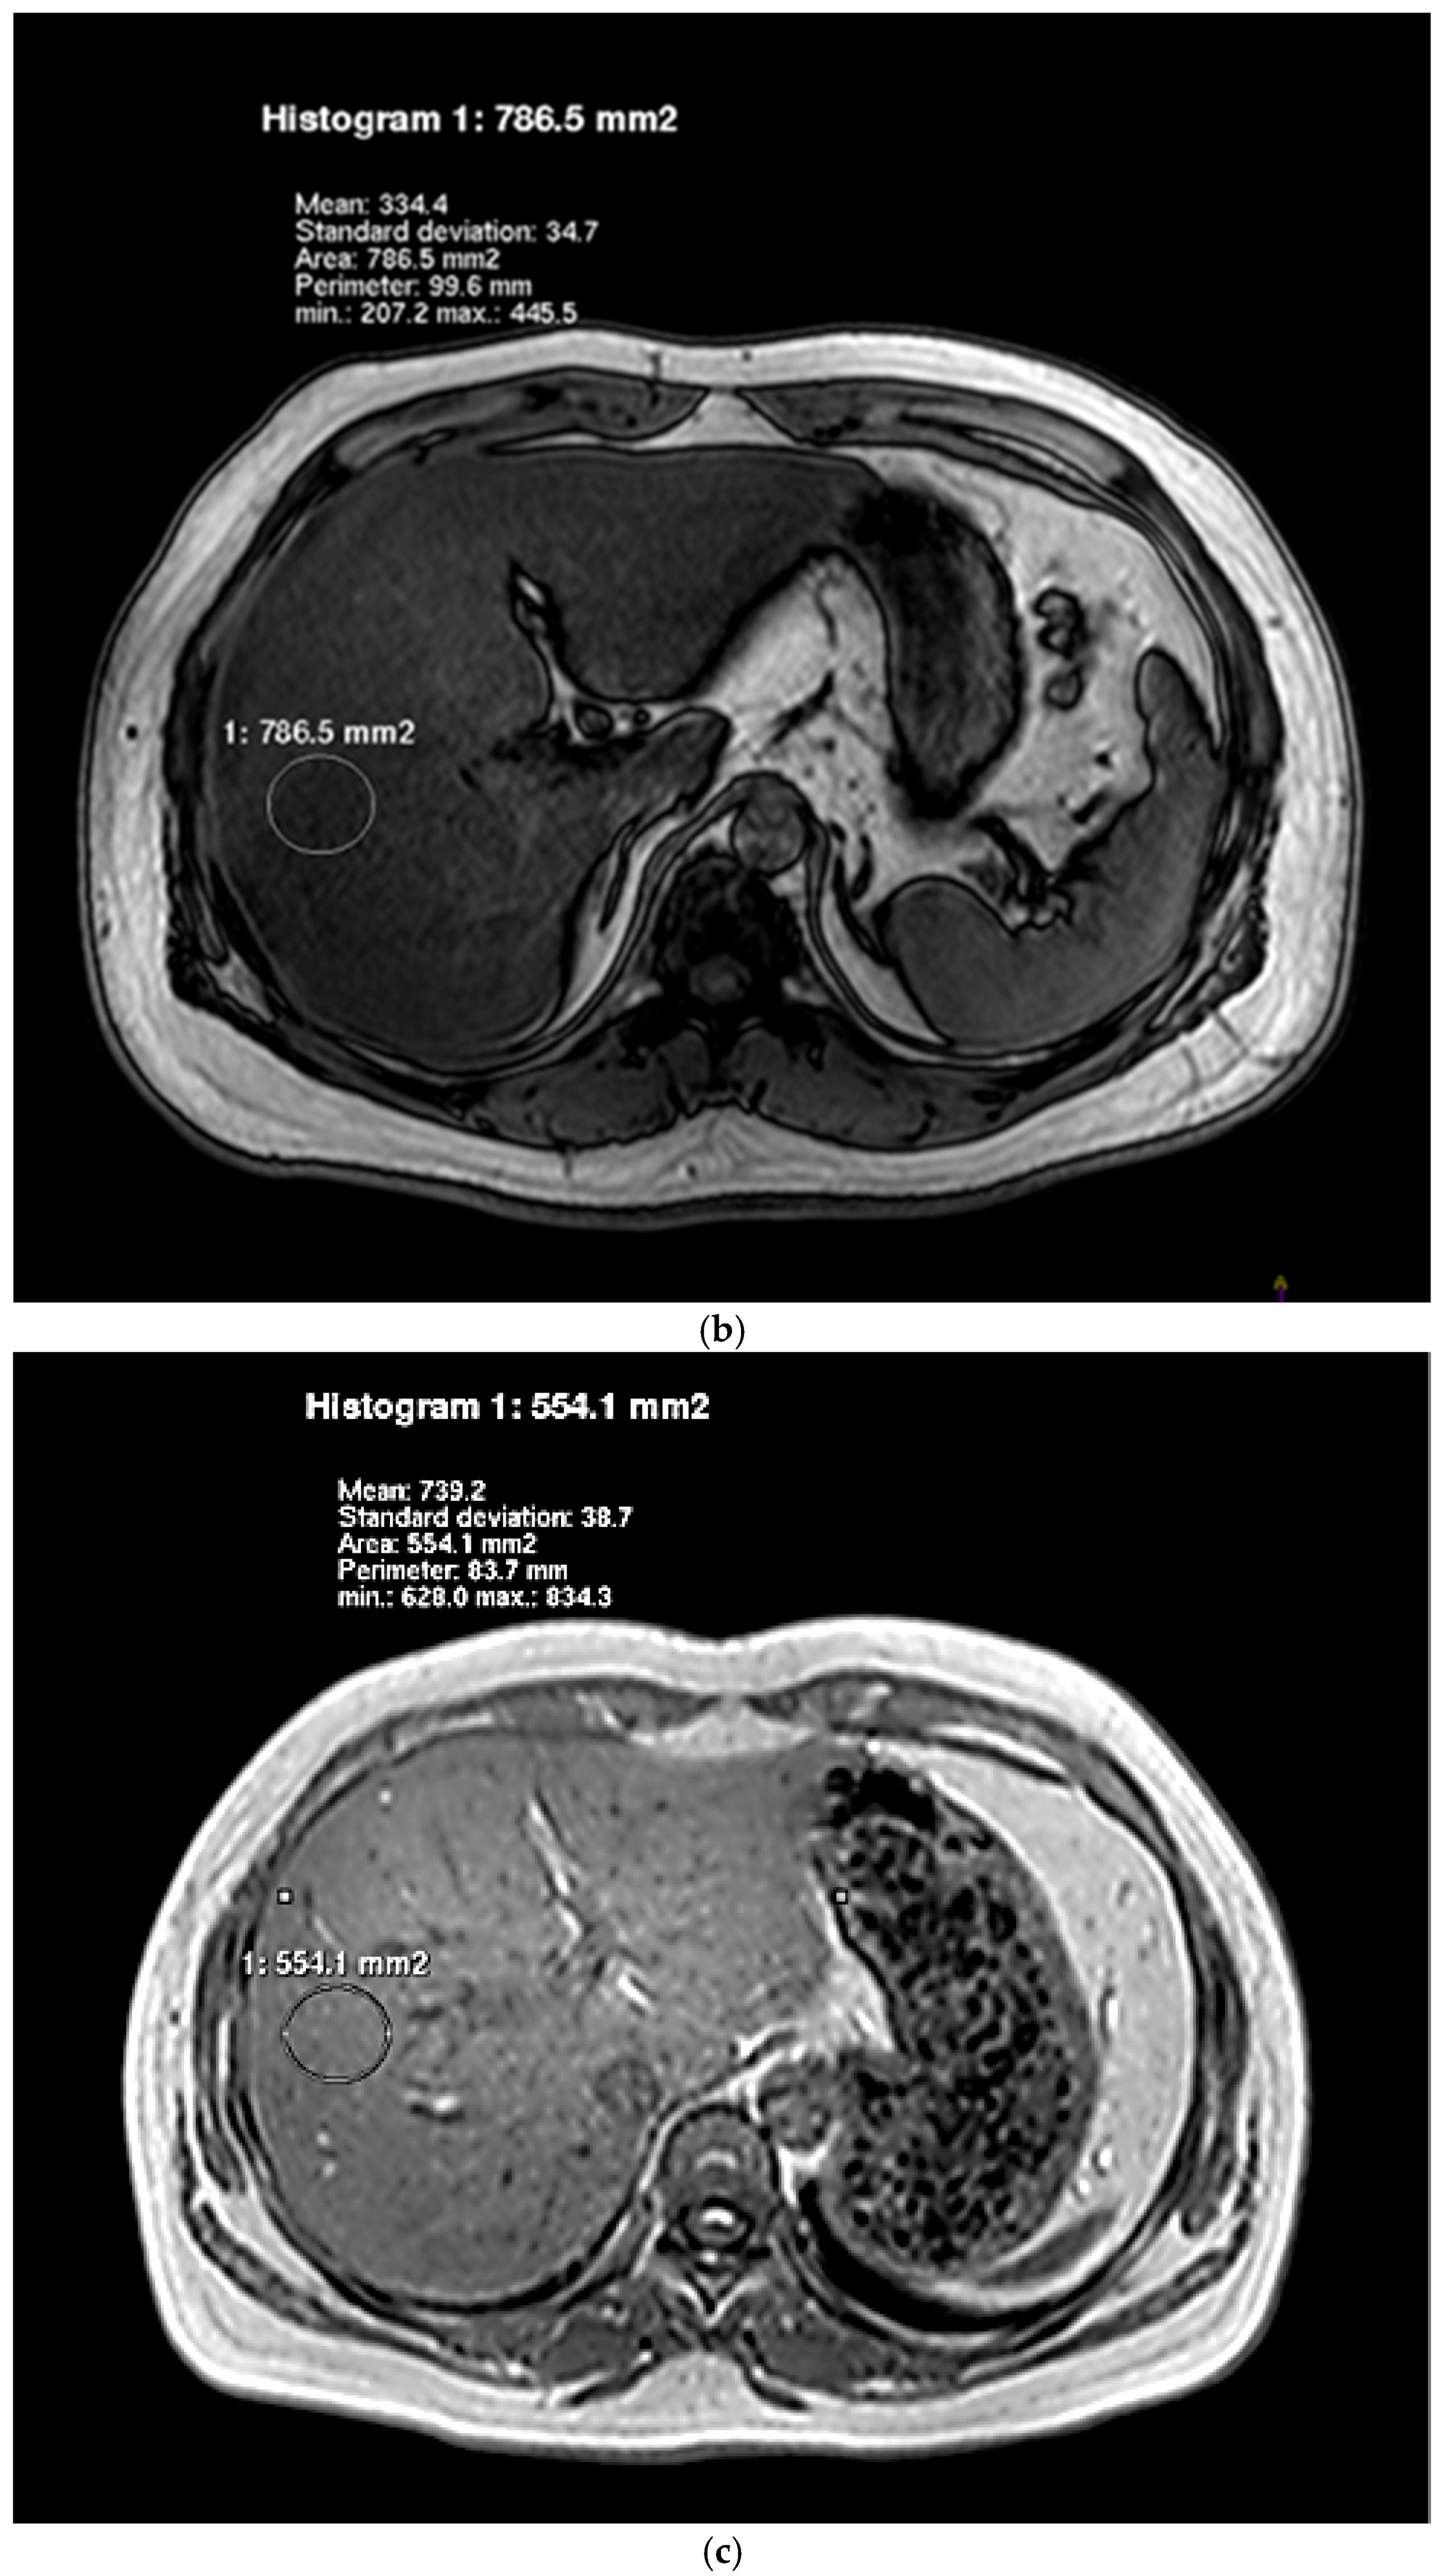

2.5. Hepatic Lipid Contents Measurements